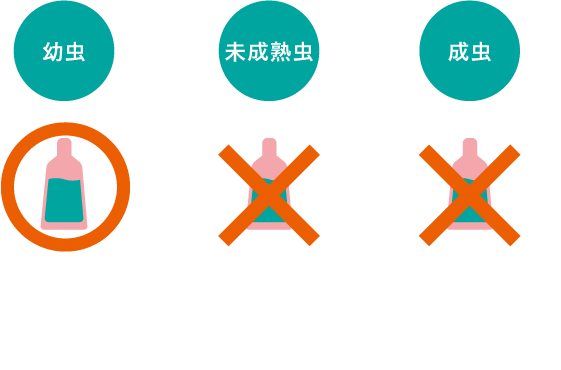

フィラリアは幼虫まではお薬で駆虫することができますが、未成熟虫、成虫になってしまうと効果がありません。

ねこがフィラリアに感染した場合、治療としてはお薬を投薬し続け幼虫が未成熟虫になるのを防ぎ、 数を減らしていく方法や、ねこの心臓から成虫を取り出す方法などがあります。

しかし、どちらもねこにとって大きな負担となり、命が危険にさらされることも。だからこそ予防が一番の対策なんです。